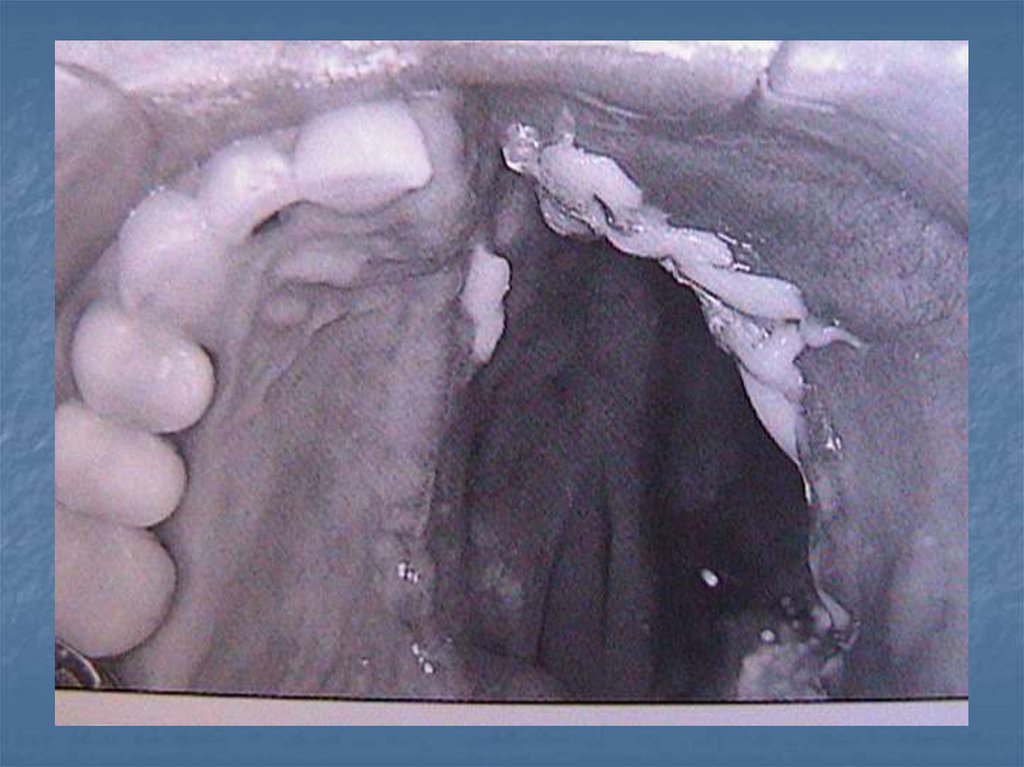

Defekt içi stabilite

oklüzyon

İmmediat protezlerin hazırlanması

Obturatörleri Etkileyen Kuvvetler-2